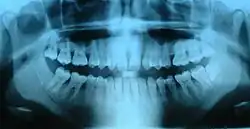

Orthopantomogram

Een orthopantomogram (in de kaakchirurgie en tandheelkunde OPT, in de radiologie OPG geheten) is een röntgenfoto van de gehele kaak, inclusief de kaakgewrichten, die zo wordt genomen dat alle tanden en kiezen daarop te zien zijn. Zowel de röntgengevoelige plaat als het röntgenapparaat draaien om het hoofd van de patiënt. Het hoofd van de patiënt wordt daarom gefixeerd.